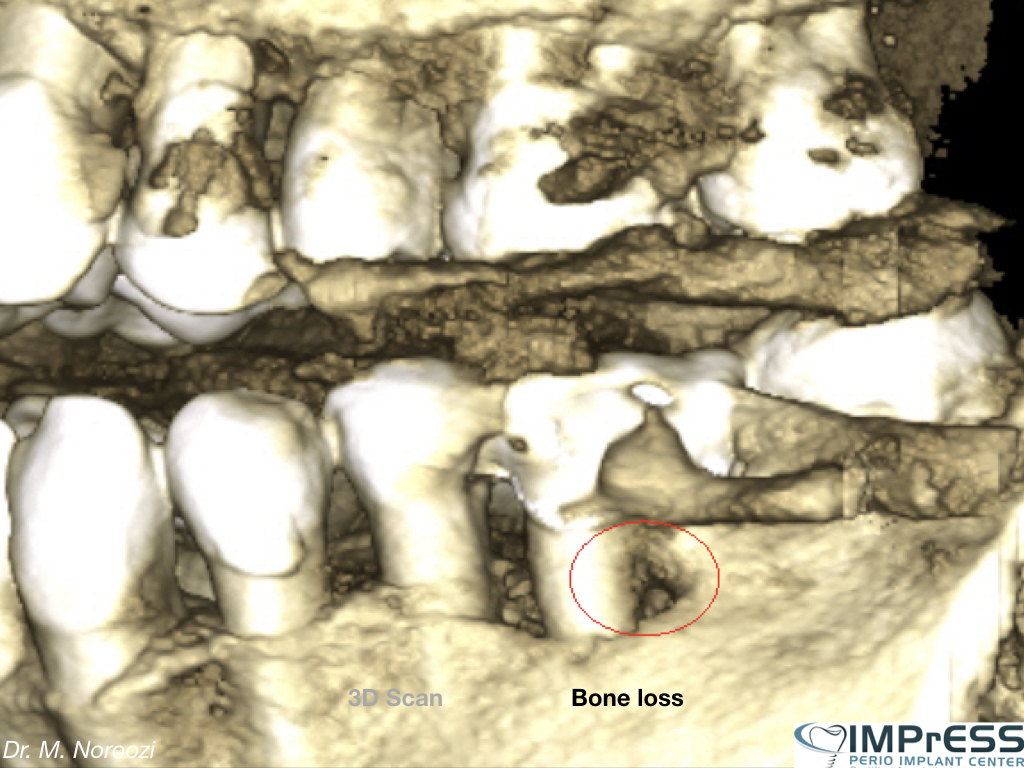

Bone Graft, Guided Bone Regeneration and Implants

Bone Graft Implants Dr Noroozi IMPRESS Perio Implant Center